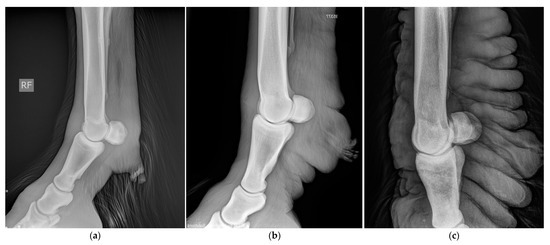

5.3. Medical Imaging